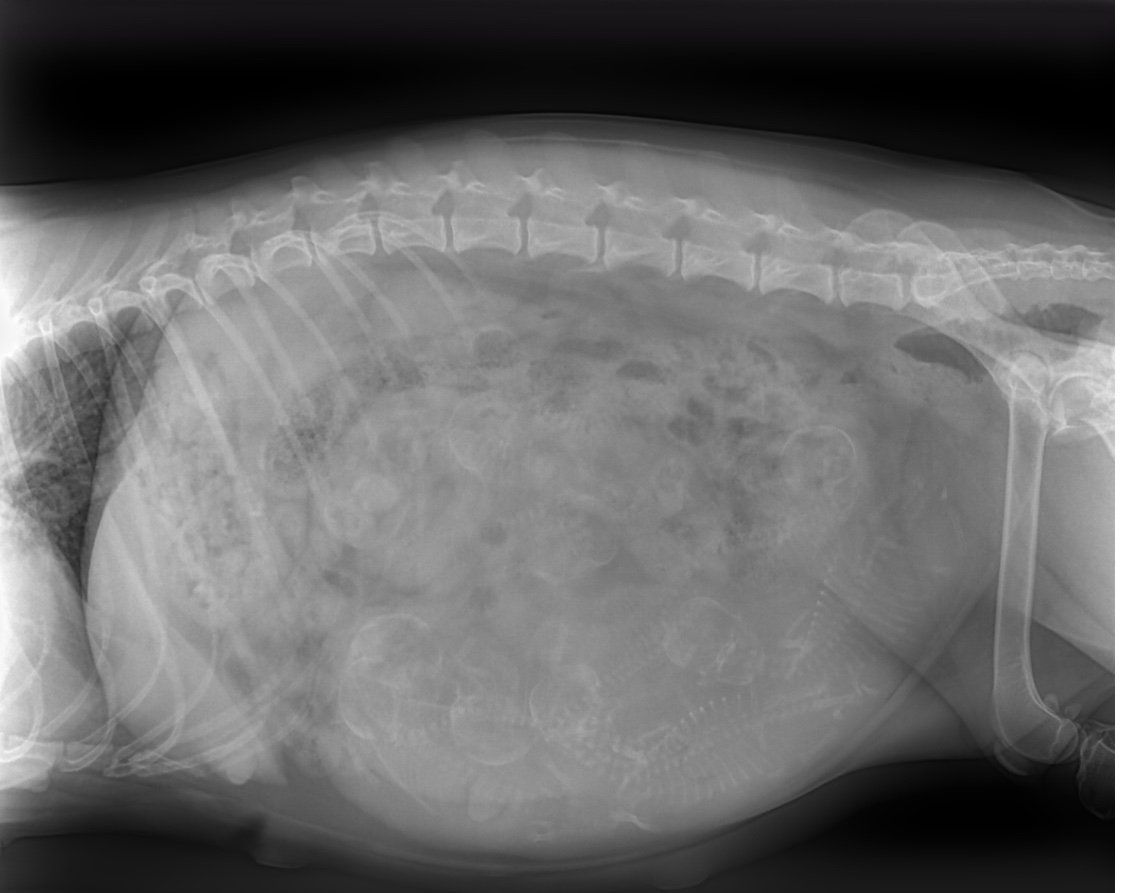

13.08.20 Heute haben wir geröntgt! Jana war recht gelassen und hat das toll mitgemacht! Es ist nicht ganz eindeutig zu erkennen, wieviele Welpen es werden. Der TA geht aber von 7-8 Welpen aus. Ich hatte mit etwas weniger gerechnet. Jetzt wird es doch wieder sehr anstrengend für Mama Jana und mich. Wir freuen uns aber schon total auf die Lütten💕. Jana geht es trotz der extremen Hitze gut. Sie muss zwar zum Spaziergang überredet werden, nimmt aber die Brombeeren unterwegs gerne mit😋